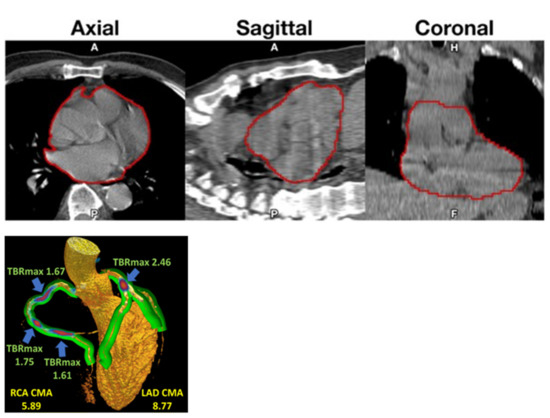

Arani et al. found a positive correlation between NaF uptake, but not FDG uptake, in the abdominal aorta and 10-year FRS in both healthy volunteers and angina pectoris patients [16], and Sorci et al. observed that global heart NaF uptake and calcium scores were higher in patients than healthy volunteers (Figure 1) and that cardiac SUVmean could to some degree discriminate between patients and controls, whereas FRS could not. They also showed that cardiac SUVmean correlated with age and BMI across females and males and increased with age and BMI [4].

Figure 1. Fused NaF-positron emission tomography/computed tomography images of patient (top) and matched control (bottom). Note that the distribution of NaF uptake in the patient does not follow only the epicardial routes of the three coronary arteries, but is more dispersed, suggesting that NaF uptake is present in the walls of the entire cardiac arterial tree (with permission from reference [4]). Coronary arterial contrast-enhanced imaging would help address the issue.

Standardization is lacking. Most centers calculated a TBR using SUVmax and/or SUVmean values divided by blood pool activity from various parts of the vascular bed, even if recorded activity varies considerably from segment to segment of the vascular bed dependent on spill-over from NaF content in adjacent bone [40]. Cardiac motion was addressed in particular by Kwiecinski et al., who measured the uptake in the proximal parts of the coronary arteries [41,42], which others have found to be suboptimal due to the limited spatial resolution of PET imaging and cardiac and respiratory movements [43]. Instead, a global assessment approach comprising the entire heart may be preferable [4,44], and perhaps a better reflection of cardiac atherosclerosis burden as a clinically more relevant measure than the NaF uptake in vulnerable coronary plaques [45,46]. Accordingly, Kwiecinki et al. proposed a novel “whole-vessel” coronary NaF approach for assessment of the “global coronary microcalcification burden” (Figure 2, left) [39]. It will be interesting to see how well this procedure corresponds with the whole-heart approach [4], which assumes that NaF is taken up only in the arterial walls and not in other tissues of the heart.

Figure 2. (Top): Volume of interest (VOI) capturing a representative heart. VOIs were thresholded to exclude voxels under −50 HU before being superimposed onto corresponding PET images (reproduced with permission from reference [4]). (Left): three-dimensional (3D) rendering of coronary CT angiography with superimposed tubular whole-vessel volumes of interest (light green) employed for evaluation of NaF uptake (blue and red). Despite the relatively lower TBRmax due to multiple foci of increased NaF activity, the coronary microcalcification activity (CMA) in the right coronary artery (RCA) is only moderately lower than in the left anterior descending (LAD) coronary artery, which presented with a very high TBRmax (with permission from reference [39]).